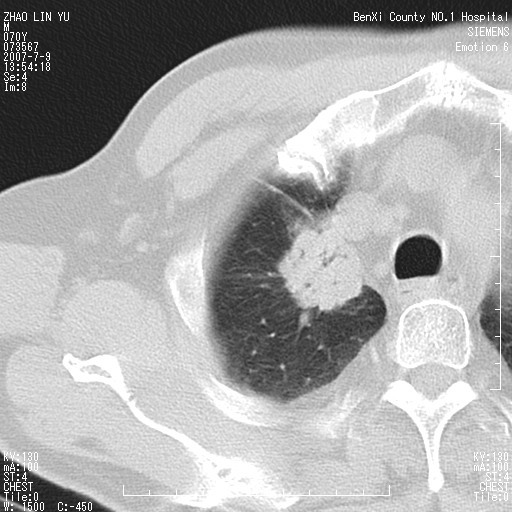

以下是引用王靖旗在2007-7-10 17:12:00的发言:[br] 男、70、咳嗽两个月,半年前换瓣手术,胸片未见异常,于昨天行x片发现右肺上野大片影,行ct扫描,这里是减薄图像,余肺正常。明天晚上会有增强扫描片,到时我会上传。[br][br] 冠状位请大家细看,应该是有意义的,[br][br] 请大家先看平扫发表意见。[br][br]

以下是引用zhangzhongshou在2007-7-10 21:43:00的发言:[br]右肺上叶周围型肺癌,以孤立型细支气管肺泡癌可能性大。